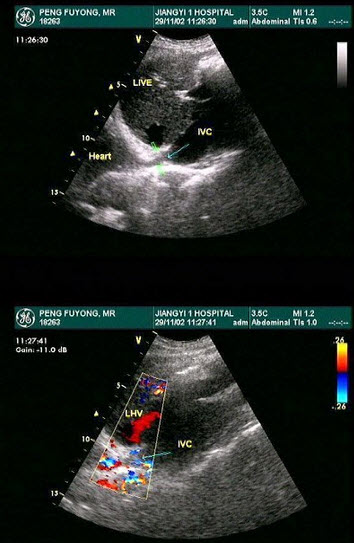

92、单项选择题

该病例最有可能诊断是()

A.布-加综合征

B.川崎病

C.动脉瘤

D.以上都不是

E.门静脉高压